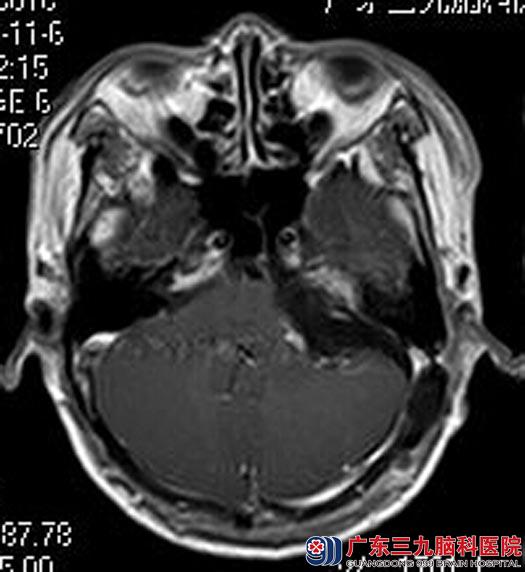

完善相关检查后,综合神经外科鲁明主任主刀,在全麻下行左侧桥小脑角区肿瘤切除术,术中见肿瘤位于左侧桥小脑角,呈囊实性改变,切开囊壁,放出淡黄色囊液,肿瘤实质部分呈黄白色,质中,血供丰富,予显微镜下电凝分块切除,术中电生理监测,左侧听神经、面神经、三叉神经与肿瘤紧密粘连,经细心分离以完整保留,肿瘤基底部位于左侧内听道,予刮匙刮除内听道内肿瘤,手术顺利。术后史先生未出现后组颅神经损伤症状,已康复出院。术后病理结果:听神经瘤。

手术后